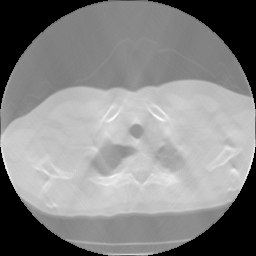

III-C2 Unsupervised Learning

To validate and evaluate the generalization of the proposed method, we adopt the network, trained on lung CT data, on the Zubal’s phantom except lung position. Fig 10 and Table II demonstrate the experiment results.

We can see the process unsupervised training have significant effect in eliminating the artifacts introduced by over fitting (fig 10 row1) and make the edges in image slightly sharper (fig 10 row2). And the data fidelity implied in loss ensures the image quality not to degrade in training (fig 10 row3). Like the results for lung CT data, our after trained network’s results have less streaking artifacts than FBP results and cartoon-like artifacts than SART-TV results. The quantitative metrics gives the same conclusion. So the after train proposed network can be transfer trained flexibly in different scanning scenes.

Refer to caption

TABLE II: Quantitative Comparsion for FBP, SART-TV and Proposed Method for Zubal CT dataset (40 slices)

FBP SART-TV Proposed

avg. PSNR(dB) 24.88 28.08 36.33

avg. SSIM 0.9598 0.9523 0.9838